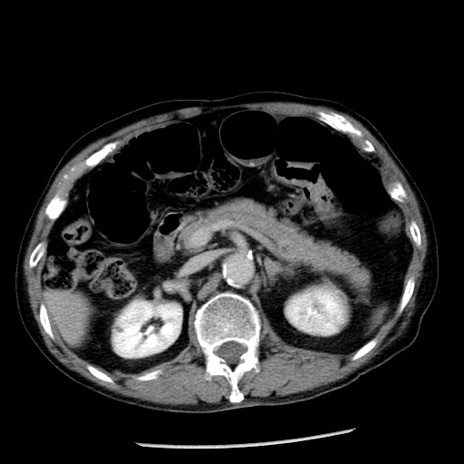

症例26(横断像)

【症例】80歳代男性

【主訴】嘔吐

【現病歴】昨晩2回嘔吐あり、今朝になっても嘔吐あり。来院。

【既往歴】胃潰瘍

【身体所見】意識清明、BT 37.6℃、BP 166/95mmHg、HR 100bpm、SpO2 97%、腹部:平坦・軟、腸蠕動音聴取良好、圧痛なし。

【データ】WBC 21900、CRP 1.46